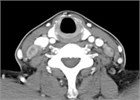

1. 原発巣の進展範囲診断にはCTに加えMRIが推奨される(推奨度2 SJG)